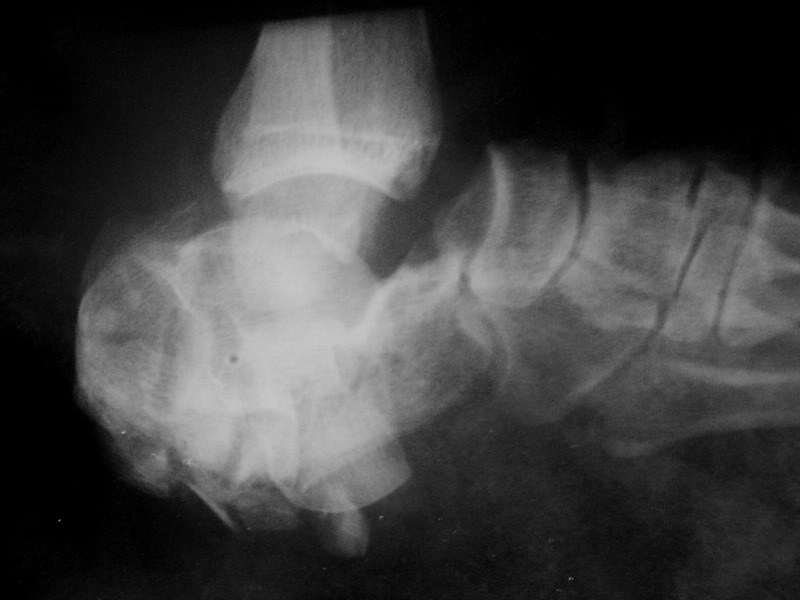

Перелом пяточной кости, вывих в суставе Шопара |

Уважаемые коллеги! Прошу вас высказать свое мнение по поводу дальнейшей тактики лечения и возможных вариантах оперативного лечения. Мужчина, 57 лет. В сентябре 2008 в результате ДТП (находился за рулем автомобиля, лобовое столкновение), получил травму левой стопы: Закрытый многооскольчатый перелом пяточной кости, вывих стопы в суставе Шопара. Лечился в районе скелетным вытяжением за пяточную кость. Процесс осложнился околоспицевой инфекцией. Сейчас в области пяточного бугра свищ со скудным гнойным отделяемым. В течение двух дней получает линкомицин. Планируется аппаратный артродез.

Рентгенограмма в боковой проекции приведена. В прямой проекции снимок малоинформативна (см. ниже).

IMGP4032а.jpg

Кроме того , как Вы оцениваете жизнеспособность тарана ? Представленные снимки свежие или это на момент травмы ? Как обстоит дело с нейроваскулярным статусом стопы на сегодняшний день ? Имеются ли контрольные снимки на этапах лечения (за что тянули ? на снимке вроде бы отверстие в таране) ?

Доброго времени дня! Спасибо за ответы. Снимки свежие. Кровоснабжение и чувстительномть стопы не страдают. На жизнеспособность таранной кости надеемся. Внешний вид - отечность пяточного бугра, на его латеральной поверхности свищ, смещение к тылу дистального отдела стопы. Фистулографию, как и КТ, МРТ, проводить не планируется (лечащий врач - не я).

Предыдущих снимков нет. Тянули, видимо, за мягкие ткани, отломки пяточной кости. Действительно, похоже на отверстие в отломках, соответствует локализации свища.